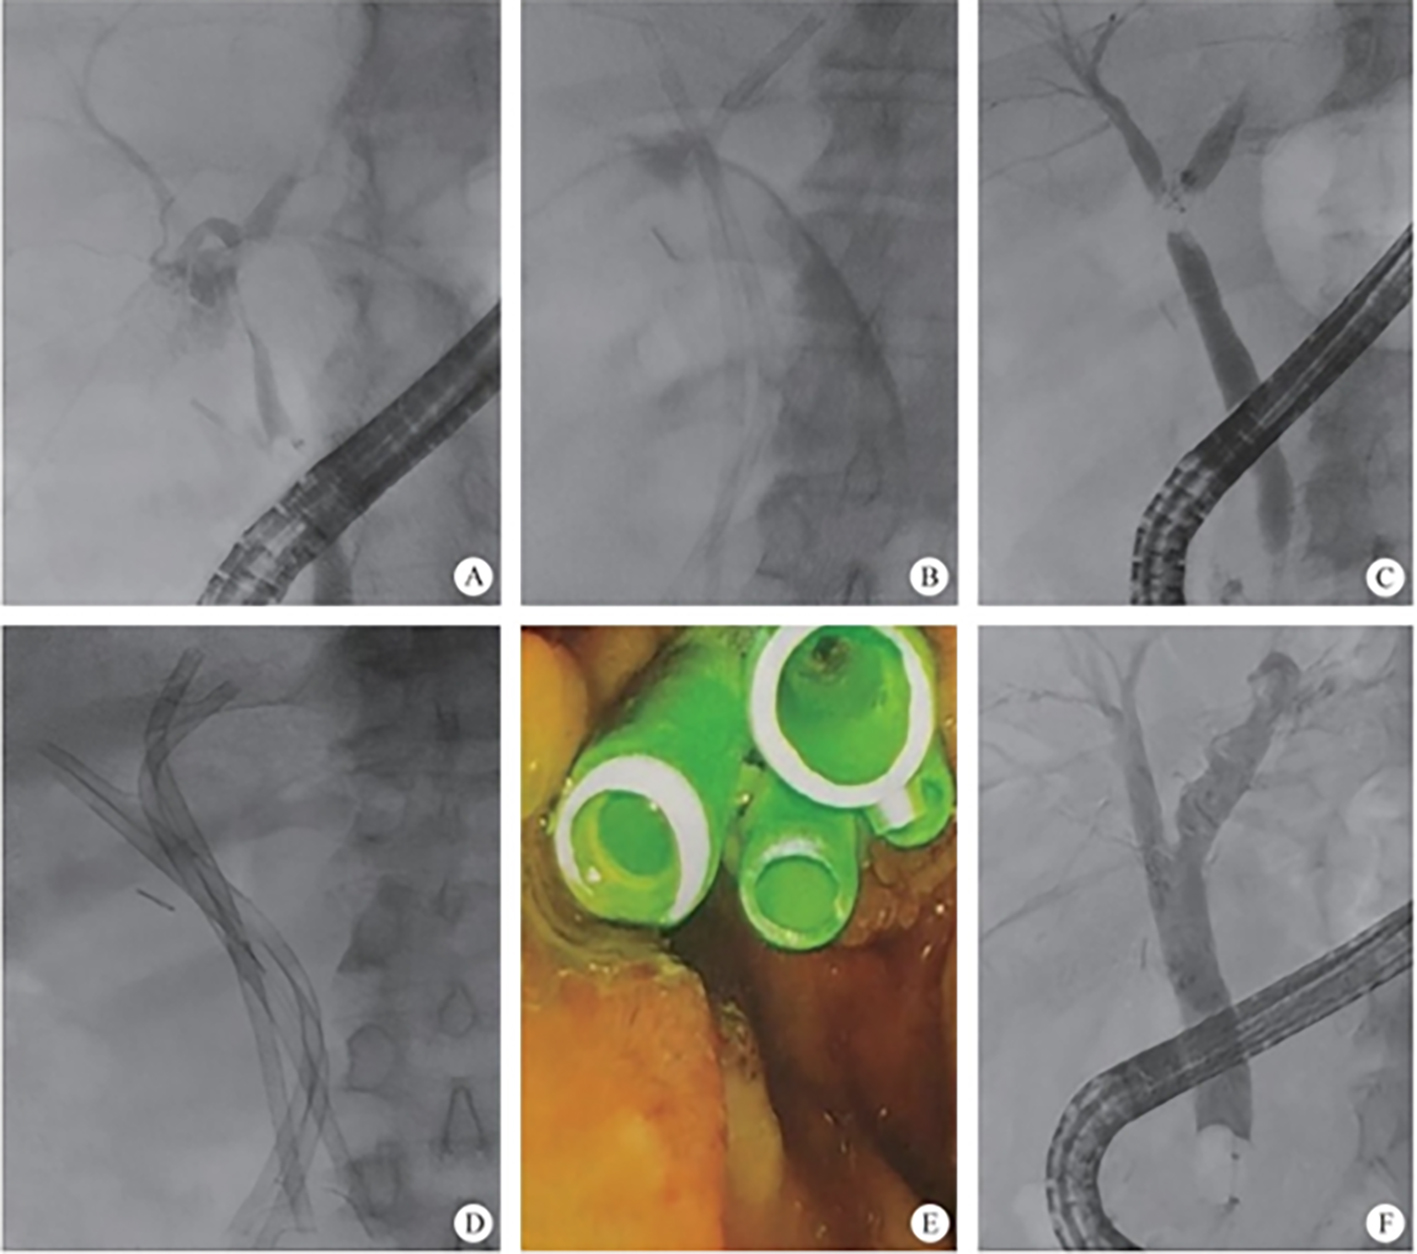

The intrahepatic bile duct is the relative blind area of SpyGlass. The treatment of intrahepatic bile ducts by retrograde transpancreatobiliary endoscopy can avoid the trauma of surgical choledochoscopy and sinus infection caused by percutaneous choledochoscopy. However, there are still few reports on the diagnosis and treatment of intrahepatic bile ducts by choledochoscopy in China and abroad, and they only concern grade-I and II intrahepatic bile ducts, even if currently the surgical choledochoscopic fiber can enter directly intrahepatic bile ducts above grade IV. In 2021, a study evaluated the effect of SpyGlass on grade-I and II intrahepatic bile duct lithotomy, whereas laser lithotripsis is performed for large or impacted gallstones at the same time. The results showed that the diagnostic rate of SpyGlass was 97.14%, the success rate of one-time lithotomy was 85.71%, the occurrence rate of complication was 8.57%, the postoperative residual stone rate was 14.28%, showing that SpyGlass can effectively diagnose and treat intrahepatic bile duct stones. But so far a multi-center study is still lacking to support its clinical promotion and application. In addition, SpyGlass can also be used to remove gallstones through the gallbladder duct while preserving it, with a high rate of stone removal, while being less traumatic, with rapid recovery and effective resumption of gallbladder function.